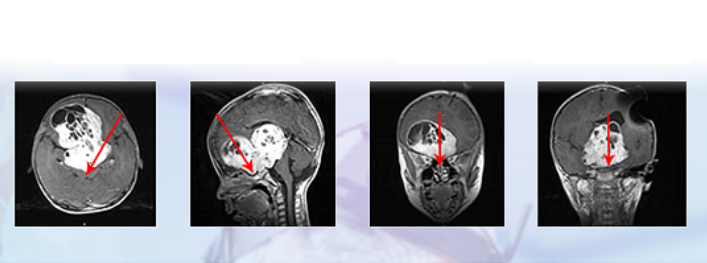

一名6岁的女童在视力检查出现问题后被转介到眼科。经检查,她的左眼视力下降(20/80)和色觉(仅限控制板)。右眼视力和色觉正常。她有一个低振幅,高频摆...

视神经胶质瘤(ONG)是较常见的原发性视神经肿瘤,通常在生命的一个十年被发现。散发性视神经胶质瘤(OPGs)通常在8岁前出现。我们的病人是ONG文献中一个没...